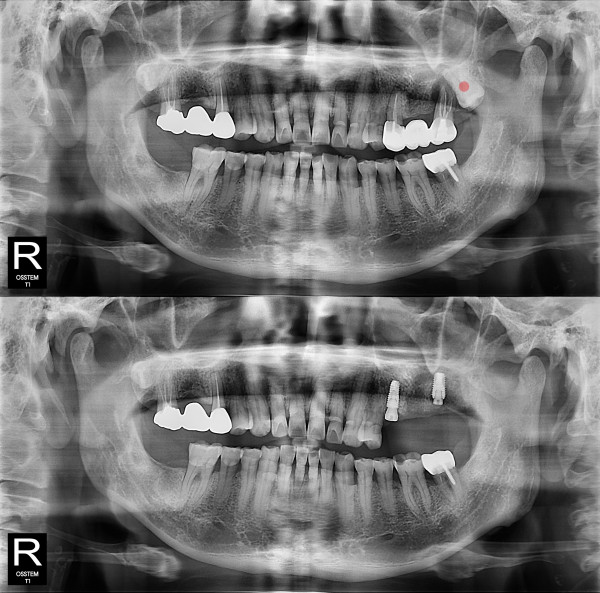

智齿拔除 完全埋伏智齿